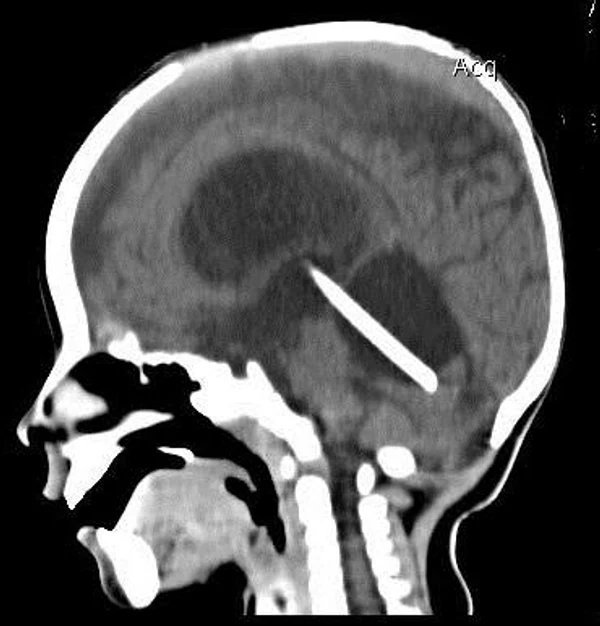

кисты, аномалии Денди-Уокера и др.Операции при внутричерепных кистах. В основном встречаются арахноидальные кисты различных локализаций и кисты сосудистых сплетений боковых желудочков. Пациентам с врождёнными кистами операции проводятся в следующих ситуациях: увеличении объема кисты в динамике, наличии клинических проявлений, компрессии и дислокации мозговых структур, наличии окклюзии ликворных путей. Нами используются 2 способа хирургического лечения кист: эндоскопическая перфорация стенок кист и открытая резекция кист. Открытая резекция кист проводится при ретроцеребеллярных арахноидальных кистах (рис. 2), при арахноидальных кистах межполушарной щели при отсутствии непосредственного контакта их стенок со стенками расширенных желудочков головного мозга и повторного увеличения кист средней черепной ямки после эндоскопической кисто-цистерностомии. Техника операции заключается в проведение краниотомии и максимальном иссечении стенок кист с созданием широкого сообщения кист с субарахноидальным пространством. Эндоскопические операции проводятся при арахноидальных кистах межножковой и пинеальной цистерн, арахноидальных кистах межполушарной щели при тесном контакте их стенок со стенками расширенной желудочковой системы (рис. 3), первично при арахноидальных кистах средней черепной ямки, а также при кистах сосудистых сплетений боковых желудочков. При арахноидальных кистах межножковой цистерны эндоскопически проводится перфорация стенок кисты, сообщая ее с просветом III желудочка и межножковой цистерной – эндоскопическая вентрикуло-кисто-цистерностомия (рис. 4). При арахноидальных кистах пинеальной цистерны проводится перфорация кисты в передне-верхних её отделах с созданием сообщения полости кисты с просветом III желудочка – эндоскопическая кисто-вентрикулостомия. С целью предотвращения облитерации сформированного отверстия иногда в полость кисты под контролем эндоскопа вводится стент перфорированный на протяжении (рис. 5, 6). Эндоскопическая кисто-цистерностомия выполняется при арахноидальных кистах средней черепной ямки. При этом создается широкое сообщение кисты с базальными цистернами. При кистах сосудистых сплетений боковых желудочков проводится их вскрытие в просвет боковых желудочков – эндоскопическая кисто-вентрикулостомия. При множественных кистах проводится их хирургическое сообщение между собой – интеркистосмия